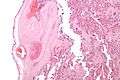

Low mag.